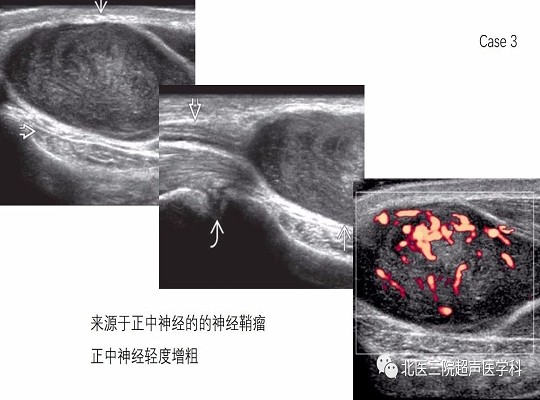

【经典超声书籍解读】周围神经肿瘤性病变(上)